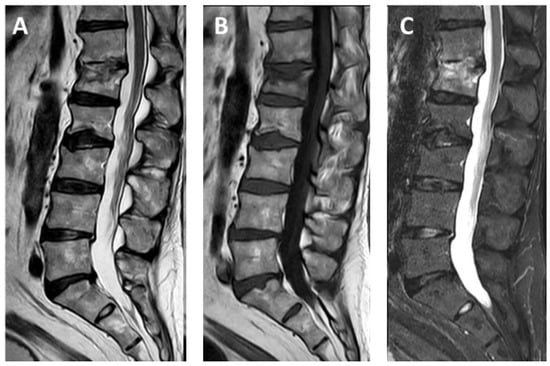

- Pusceddu, C.; Faiella, E.; Derudas, D.; Ballicu, N.; Melis, L.; Zedda, S.; Marsico, S. Re-expansion of vertebral compression fractures in patients with multiple myeloma with percutaneous vertebroplasty using spinejack implants: A preliminary and retrospective study. Front. Surg. 2023, 10, 1121981. [Google Scholar] [CrossRef]